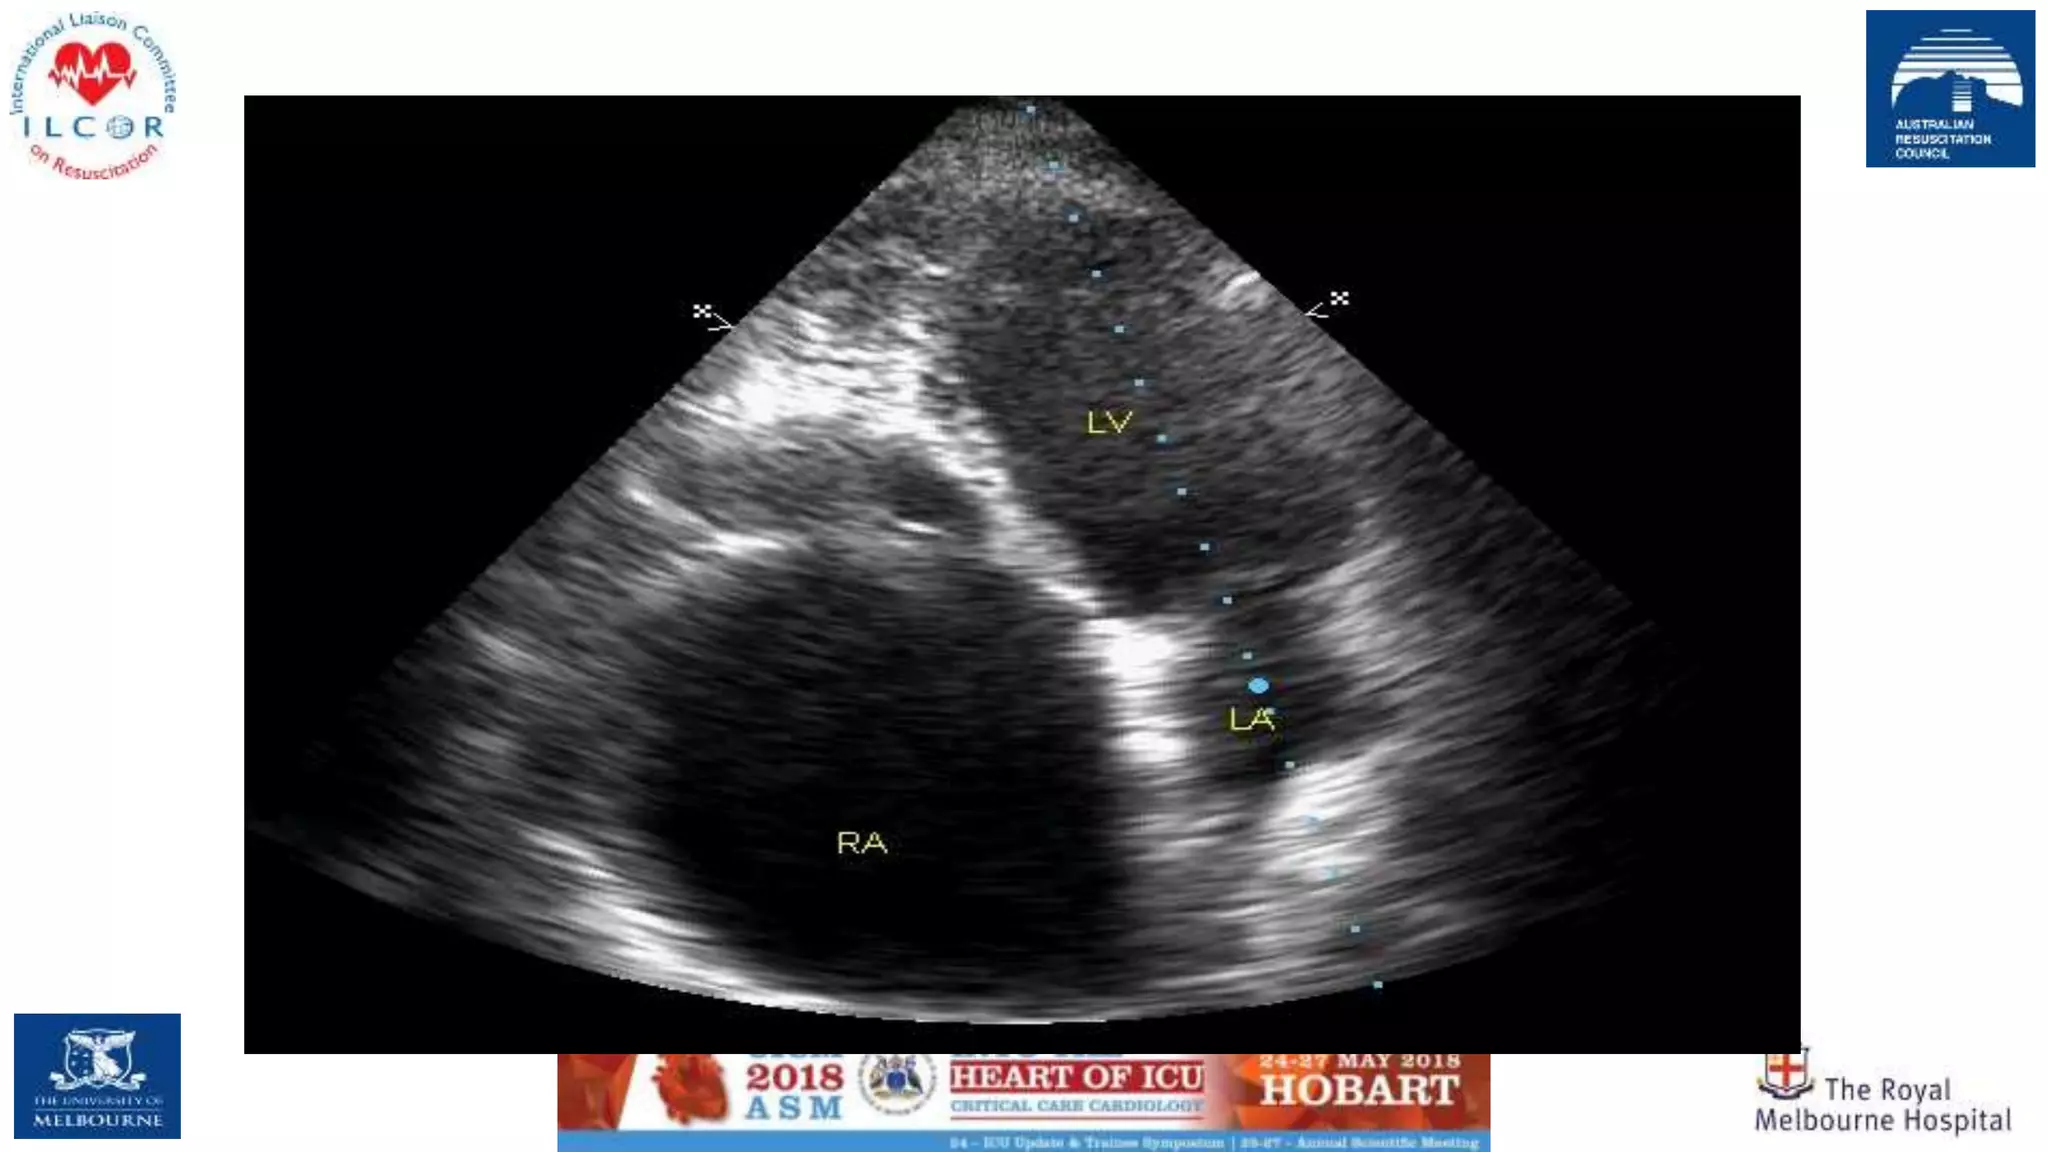

Main utility of POCUS in CA is suggested in non-shockable rhythms (i.e., pulseless electrical activity and

asystolia), aiming at identifying reversible causes of CA, such as tamponade, pulmonary embolism,

hypovolemia and tension pneumothorax

Specific conditions that can be diagnosed/excluded

by echo

• regional or global wall motion abnormalities

• pulmonary thromboembolism

• pericardial tamponade

• pacemaker capture,

• unexpected VF

• acute valvular insufficiency (eg. papillary muscle),

• ventricular rupture,

• aortic dissection

• hypovolemia and

• tension pneumothorax.